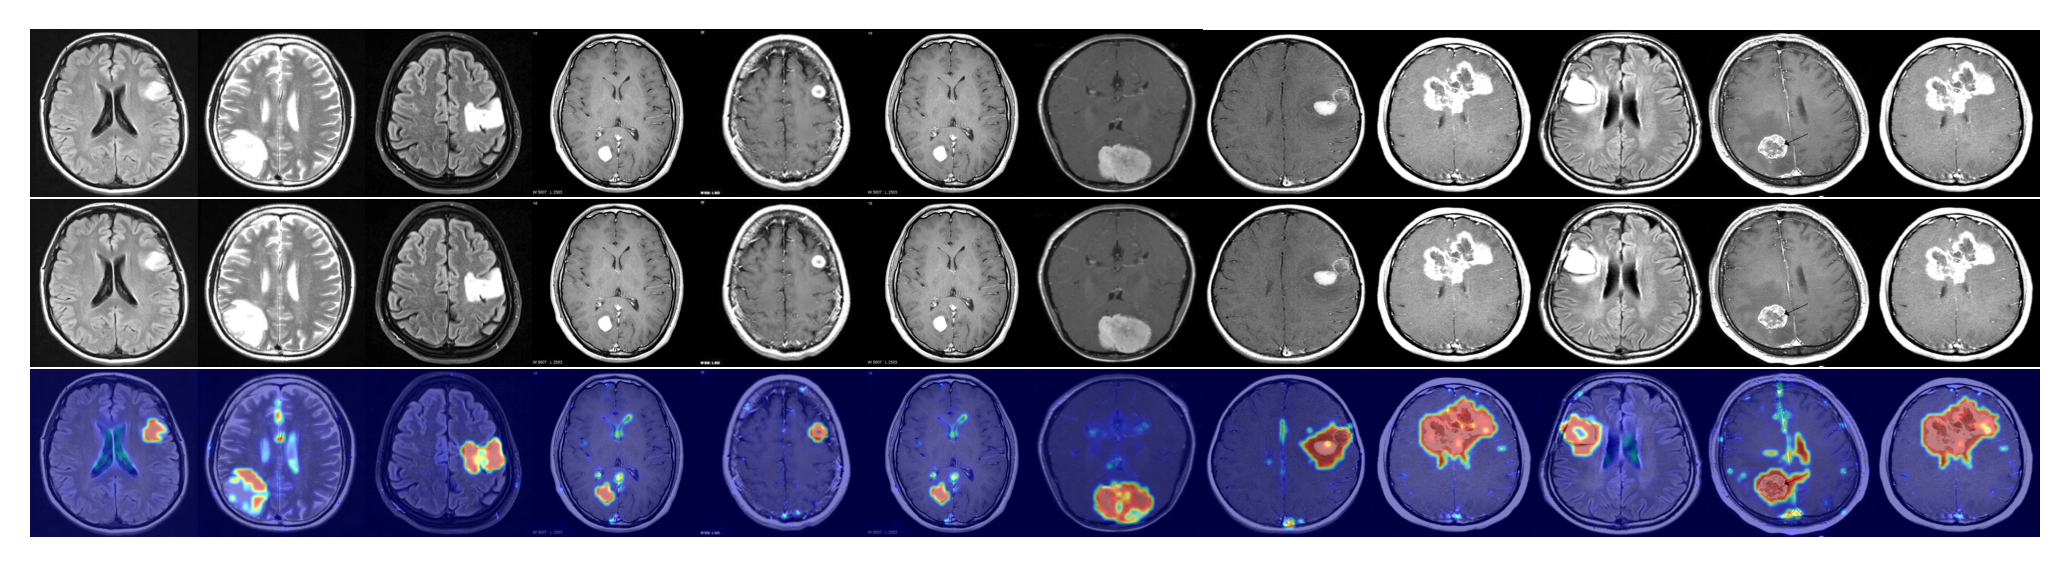

To evaluate the generalization ability of our model, we further examine the ZSAD performance of AnomalyCLIP on 10 medical image datasets of different organs across different imaging devices. Table 2 shows the results, where learning-based methods, including AnomalyCLIP, VAND and CoOp, are all tuned using MVTec AD data. It is remarkable that methods like AnomalyCLIP and VAND obtain promising ZSAD performance on various medical image datasets, even though they are tuned using a defect detection dataset. Among all these methods, AnomalyCLIP is the best performer due to its strong generalization brought by object-agnostic prompt learning. As illustrated in Fig. 4, AnomalyCLIP can accurately detect various types of anomalies in diverse medical images, such as skin cancer regions in photography images, colon polyps in endoscopy images, thyroid nodules in ultrasound images, and brain tumors in MRI images, having substantially better performance in locating the abnormal lesion/tumor regions than the other two methods WinCLIP and VAND. This again demonstrates the superior ZSAD performance of AnomalyCLIP in datasets of highly diverse object semantics from medical imaging domains.

Refer to caption

Figure 4: Segmentation visualization.

Anomaly score map for different datasets.

In addition to the similarity score for anomaly classification, we also visualize the anomaly score maps to present the strong anomaly segmentation ability of AnomalyCLIP. Specifically, we visualize the industrial object class: hazelnut, pill, and screw from MVTec AD; candle, chewinggum, capsule, cashew, pcb, and pip fryum from Visa; bracket, metal plate, and tube from MPDD. We also visualize the industrial texture: grid, leather, carpet, tile, wood, and zipper. In addition, we visualize the segmentation in medical domain across photography, endoscopy, and radiology images: skin cancer detection from ISIC; thyroid nodule detection from TN3K; colon polyp detection from Kvasir; brain tumor detection from Br35H.

Figure 36: Anomaly score maps for the data subset brain. The first row represents the input, and we circle the anomaly regions in the second row. The last row presents the segmentation results from AnomalyCLIP.